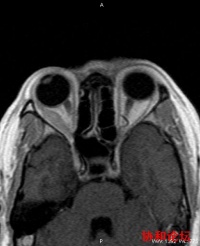

外直肌和上、下斜肌。它们由动眼神经、滑车神经和外展神经所支配,内、外直肌负责眼球向内或外转动;上、下直肌收缩时,眼球上转或下转,同时还使眼球内转;上斜肌主要使眼球内旋,同时还使眼球下转和外转;下斜肌主要使眼球外转,同时还使眼球上转和外转。这六条肌肉互相密切配合,使眼球协调一致地上下左右自由转动。当我们平时动脑筋时,眼球就会滴溜溜地转动;当我们心不在焉时,眼球就会漫无目的的转动。人的内心活动也可以从眼球的转动中表现出来。眼球在向各个方向转动时,总有一条以上肌肉在起主要作用,其他几条肌肉起协调作用。双眼的动作必须一致,当眼球向右注视时,右外直肌和左内直肌必须同时相等地收缩,否则就不能获得双眼单视。但是当这支配眼球转动的六条肌肉中只要有一条或几条发炎、外伤或神经障碍,双眼肌肉动作就不协调,如右外直肌收缩了,而左内直肌收缩慢了一点或收缩力量不够,眼球的转动就会受到限制,或使眼球偏向一侧,形成斜视,这时看东西就会特别费劲;或一个物体可以看成两个,造成视物双影,即复视。

支配眼球转动的六条肌肉中只要有一条或几条发炎、外伤或神经障碍,双眼肌肉动作就不协调,如右外直肌收缩了,而左内直肌收缩慢了一点或收缩力量不够,眼球的转动就会受到限制,或使眼球偏向一侧,形成斜视,这时看东西就会特别费劲;或一个物体可以看成两个,造成视物双影,即复视。

复视的原因很多,大抵是眼睛的外眼肌无力或麻痹所引起,而外眼肌是由脑神经所控制,所以脑神经或大脑本身的疾病都可能引起复视。

复视产生的原理是一只眼睛的影像落在黄斑部的小凹,而另一眼的影像却不落在小凹上。落在小凹上的影像永远比不落在小凹上的影像清晰,于是形成两个影像。